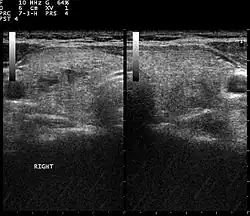

Ultrazvuk štítné žlázy

Při dalších vyšetřeních pacient podstupuje sonografii štítné žlázy,[7] při kterém se zjišťují uzly a útvary ve štítné žláze mimo normu. Tyto útvary musí být včas podchyceny a pravidelně kontrolovány lékařem, aby nedošlo k rakovině štítné žlázy.